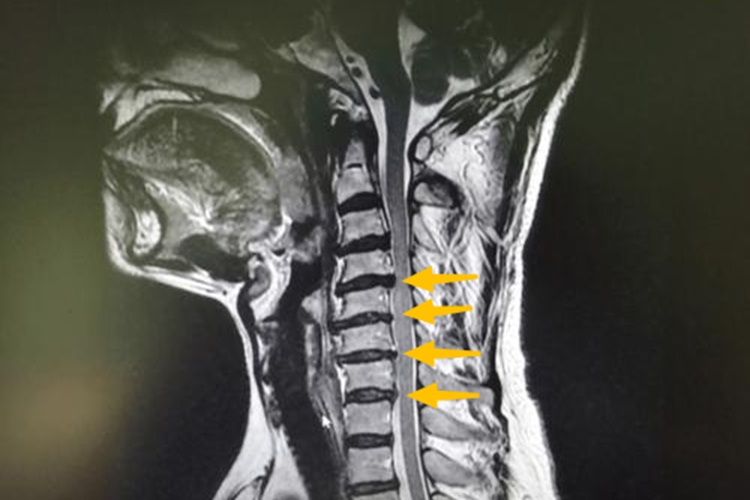

颈3-颈7椎间盘突出可表现为在轻微外力作用下或无明确诱因出现颈肩痛、上肢痛,或者肢体不同程度的感觉、运动障碍。一般通过X线、CT等影像学检查明确诊断,影像学检查可见颈椎曲度僵直,颈3-颈7椎间隙变窄、椎间盘有异常突出及颈椎管受到侵占的征象。

颈椎间盘突出主要是由于长期低头工作、劳累等因素导致颈椎间盘退变,后侧纤维环部分损伤或断裂,在轻微外力下使颈椎过伸或过屈运动,使椎间盘纤维环突然承受较大的牵张力,导致其完全断裂,髓核组织从纤维环破裂处经后纵韧带突入椎管,引起颈3-颈7椎间盘突出,压迫脊髓和神经根进而产生相应症状和体征。